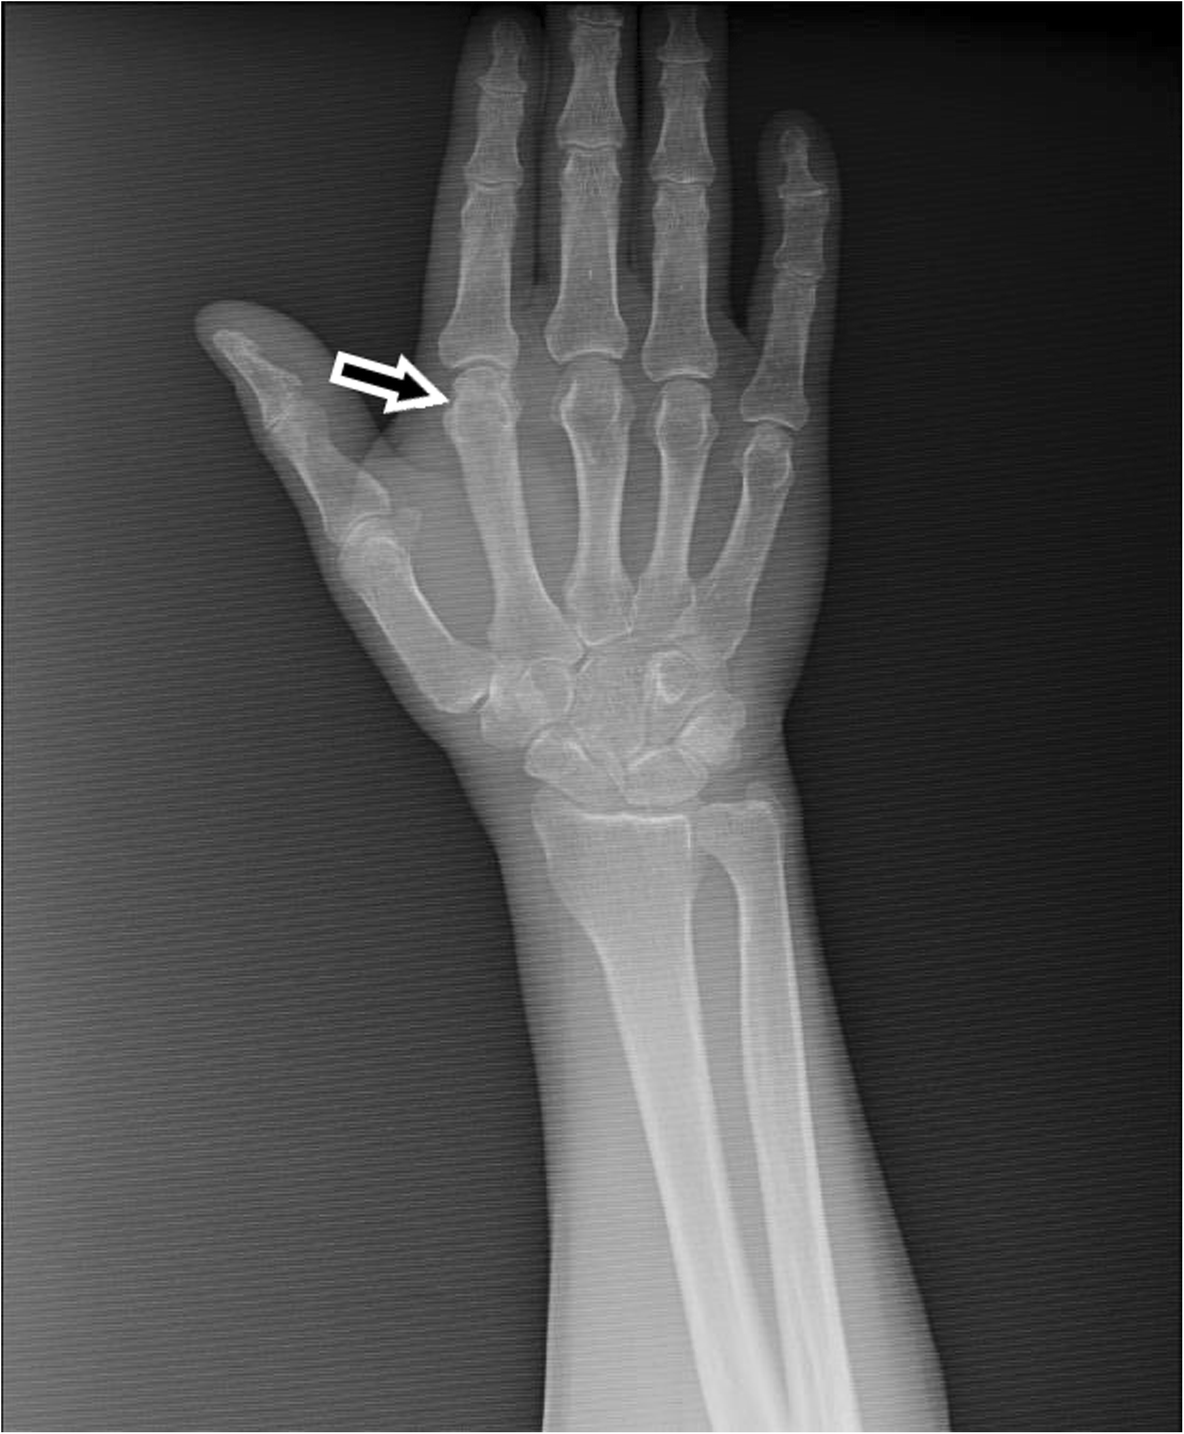

Fig. 1From: A case with Behçet’s disease involving erosive Metacarpophalangeal joint arthritis: the value of ultrasonography in the diagnosis of an ErosionConventional radiograph of the right hand and second MCP joint of our patient. The arrow shows the suspected erosion in the second MCP jointBack to article page